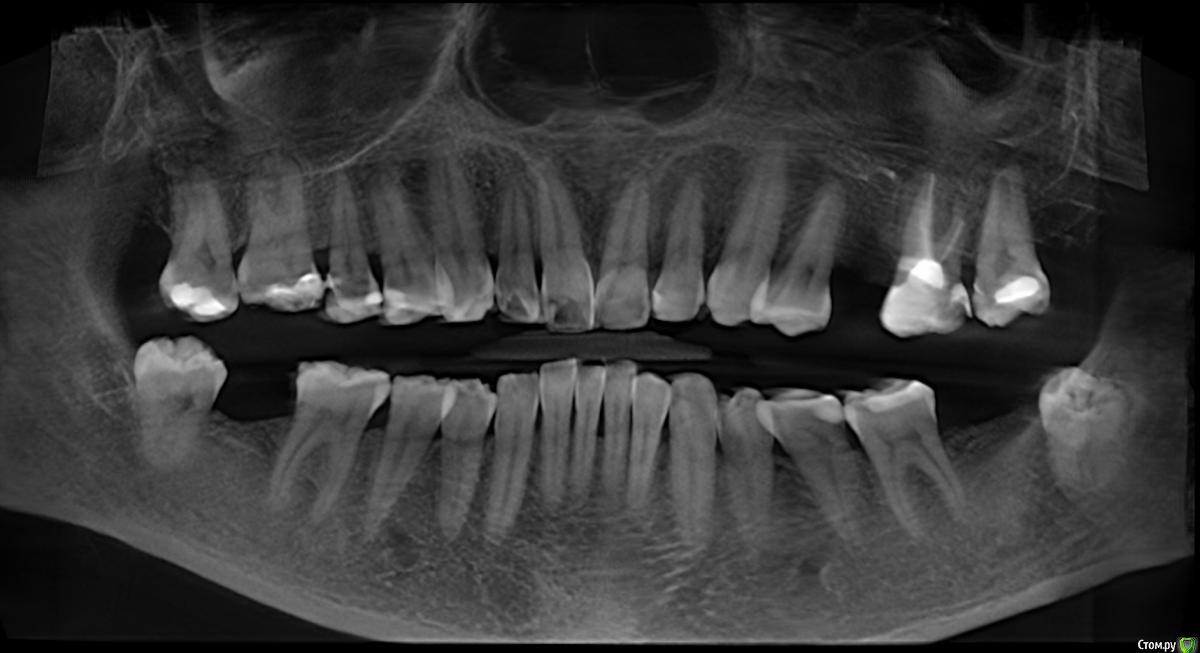

Dmitry DK Опубликовано 31 августа, 2019 Поделиться Опубликовано 31 августа, 2019 Доброго дня! Первичное обращение пациентки было связано с отсутствием 25 зуба, эстетические нарушения слизистой, клиновидные деф-ты в области других зубов - не смущали.В итоге решили, раз проводим операцию ( импл + ССТ ), закроем попутно и рец на верхней челюсти.Реставрацию на 21 зуб все не ставит... Приятных тебе выходных! ) Пациентка проходила лечение 2,5 года назад, пришла на проф осмотр 7 Ссылка на комментарий

Dmitry DK Опубликовано 4 сентября, 2019 Автор Поделиться Опубликовано 4 сентября, 2019 так нужно было его просто глубже поставитьБыли такие мысли)Имплантат упёрся в нижнюю стенку синус. Весь винт с полированной частью 9,8 мм, шероховатая часть - 8 мм, от небной стеньки до синуса - 8 мм. Выбор был 1) закрытый синус, глубже платформа 2) выше платформа, без синусаВторой вариант выбран только по причине низких эстетических требований пациентки. 1 Ссылка на комментарий